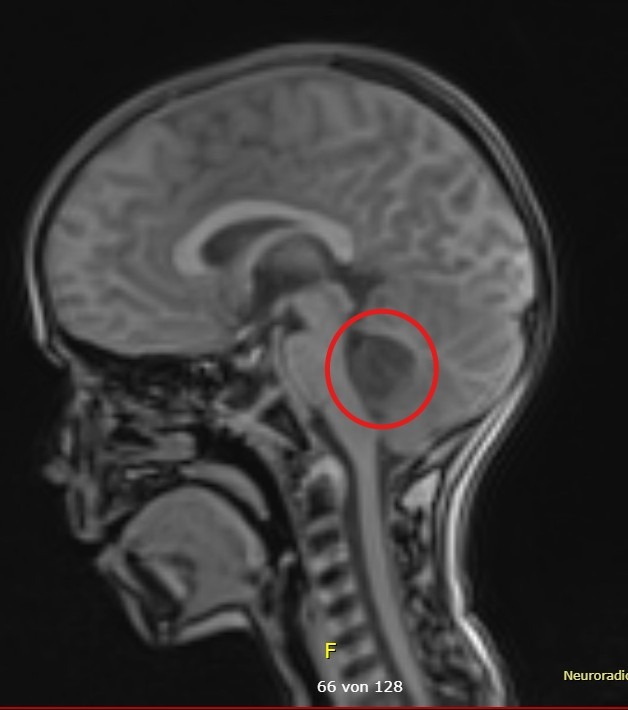

Das Medulloblastom ist ein hochgradig bösartiger Hirntumor, der meist im Kleinhirn entsteht und vor allem bei Kindern auftritt. Es gehört zur Gruppe der embryonalen Tumoren des Zentralnervensystems, da es aus unreifen, undifferenzierten Zellen hervorgeht. Die Subtypen haben höchst unterschiedliche Prognosen.

Medulloblastoma is a highly malignant brain tumor that usually forms in the cerebellum and mainly affects children. It belongs to a group of embryonal tumors of the central nervous system because it arises from immature, undifferentiated cells. The different subtypes have very different prognoses.